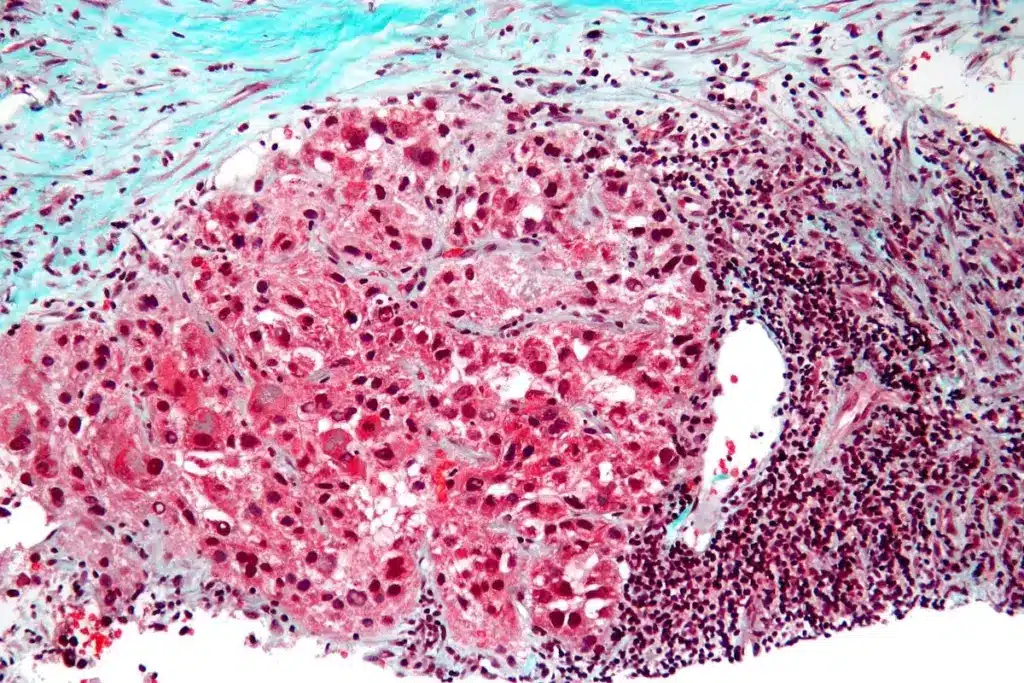

Biopsy and Histopathological Examination

Biopsy and histopathological examination are the top ways to diagnose hepatobiliary cancers. These steps involve:

- Fine-needle aspiration biopsy: Takes tissue samples from suspicious areas.

- Histopathological analysis: Looks at tissue samples to find out if there’s cancer and what type.